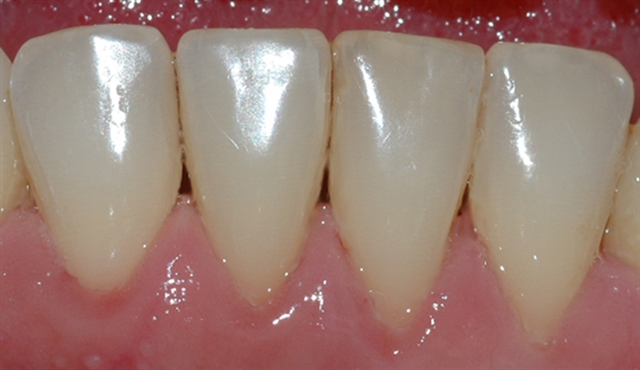

• Biletet viser tilhøva i underkjeven etter at tannstein og misfarging er fjerna.